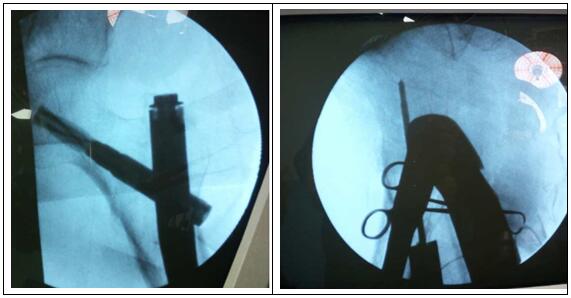

圖片二:(術中照片)

科主任楊志奎帶領曹熙、田濤、安蒙蒙、張凱迪醫師,經充分討論,考慮到患者高齡,合并高血壓、冠心病等多種基礎疾病。自身恢復能力不強,身體機能較差,已承擔不起傳統開放性手術所帶來的創傷。為改善患者生活質量,再次站立起來,根據骨折類型,為老人選擇行閉合復位股骨近端骨折PFNA髓內內固定方式。手術時長約35分鐘,術中透視骨折復位滿意,內固定裝置位置適當。術后第1天,即指導患者行左髖、膝關節屈伸活動鍛煉,術后第2天可坐起。